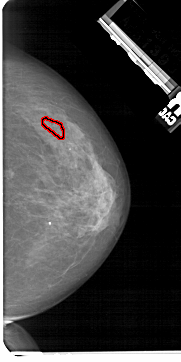

A_1465_1.RIGHT_MLO

FILE: A_1465_1.RIGHT_MLO.OVERLAY

TOTAL_ABNORMALITIES 1

ABNORMALITY 1

LESION_TYPE CALCIFICATION TYPE FINE_LINEAR_BRANCHING DISTRIBUTION LINEAR

ASSESSMENT 5

SUBTLETY 3

PATHOLOGY MALIGNANT

TOTAL_OUTLINES 1

BOUNDARY